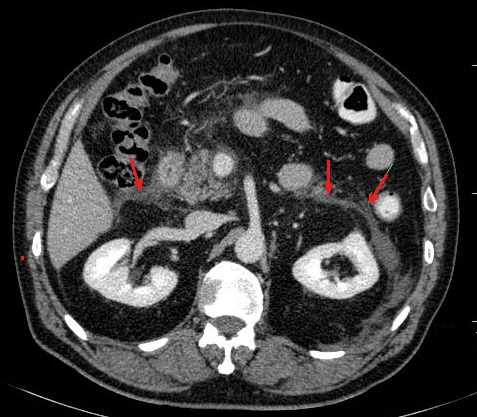

Image radiologique TDM

arteriel phase d'une pancreatite necrosant

hemoragique : Pancreas en volumineuse , presence des

foyers de necrose , hemorragique et exudative a

hypodense ,absence ou moindre de rehaussement situe

intra et extra pancreatique |